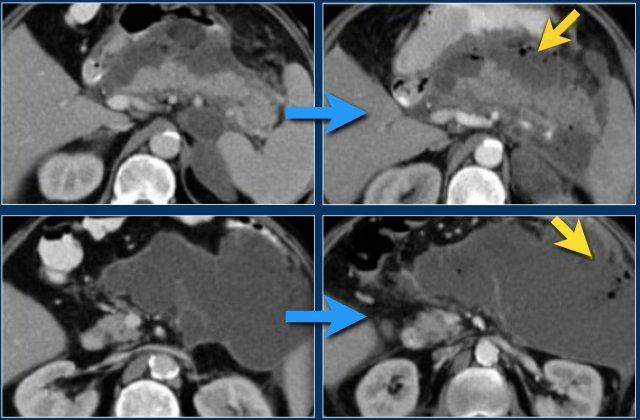

Các dấu hiệu bao gồm:

- Tụy ngấm thuốc bình thường toàn bộ.

- Các ổ dịch quanh tụy lan rộng, có tỷ trọng dạng lỏng và không lỏng trên CT.

- Có ít nhất hai ổ dịch, nhưng không có hoại tử nhu mô tụy (CTSI: 4).

- Vào ngày thứ 18, các ổ dịch quanh tụy mở rộng và xuất hiện thành không hoàn toàn.

Vào ngày thứ 5, ổ dịch này có thể được chẩn đoán là ổ hoại tử cấp tính có khả năng cao.

Vào ngày thứ 18, thành chưa hoàn toàn, nhưng có thể dự đoán rằng trong vài ngày tới đây sẽ trở thành ổ hoại tử được bao bọc với thành hoàn chỉnh.

Khi các ổ dịch quanh tụy tồn tại dai dẳng hoặc tăng kích thước, thường là do sự hiện diện của hoại tử mỡ.

Do mỡ không ngấm thuốc trên CT, việc chẩn đoán hoại tử mỡ có thể gặp khó khăn.

Ở bệnh nhân này, tụy ngấm thuốc bình thường với các ổ hoại tử cấp tính không đồng nhất có vách ngăn xung quanh, có tỷ trọng dịch và mỡ.

Đây có thể là hoại tử mô quanh tụy.

Hai tuần sau, xuất hiện các bóng khí trong ổ dịch quanh tụy, phù hợp với ổ hoại tử cấp tính nhiễm trùng.

Bệnh nhân này được phẫu thuật.

Phẫu thuật viên đã lấy ra một lượng lớn mô hoại tử và ước tính đã cắt bỏ hơn 90% tụy.

Tiếp tục xem hình ảnh tiếp theo.

Đáng chú ý, CT thực hiện 6 tháng sau phẫu thuật cho thấy tụy bình thường.

Điều này cho thấy rằng trong phẫu thuật, việc phân biệt giữa hoại tử nhu mô tụy và hoại tử mô quanh tụy đôi khi là không thể.